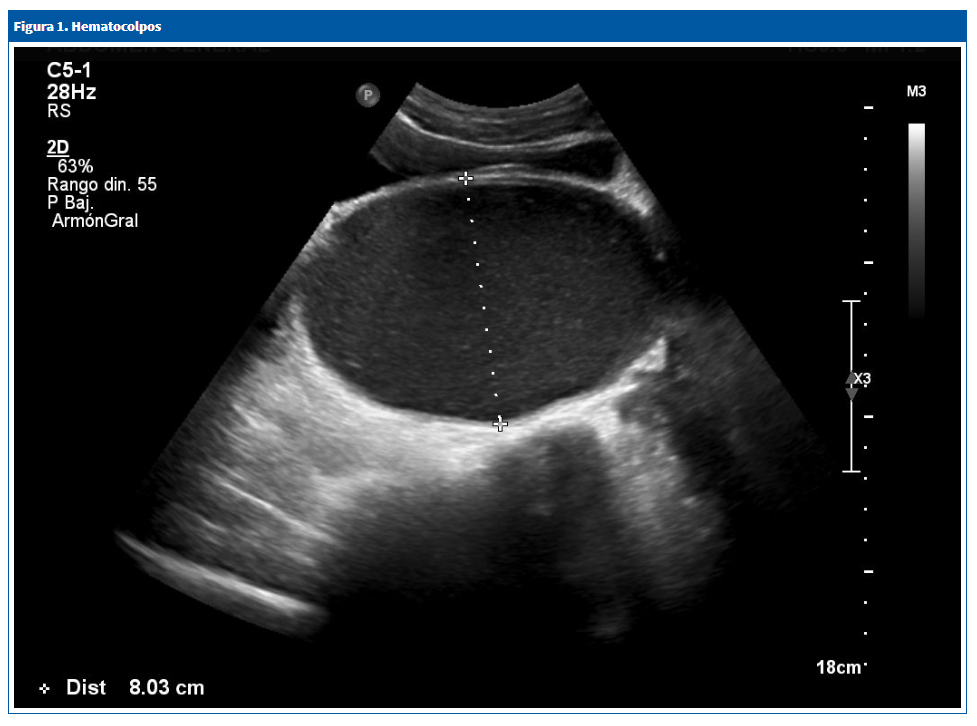

A los diez días acude de nuevo por dolor abdominal intenso que no cede con analgésicos, la despierta por la noche y tiene estreñimiento desde hace un mes. No refiere síntomas miccionales. En la exploración, el estado general es bueno, está afebril, con cardiorrespiratorio normal; se aprecia una gran tumoración abdominal móvil, fluctuante, como si tuviera contenido líquido, de forma alargada, de un tamaño aproximado de 7 × 4 cm, localizada en hipogastrio y fosa iliaca izquierda. Se solicita una ecografía abdominal urgente, en la que se observa una voluminosa lesión quística que ocupa el hipogastrio por detrás de la vejiga, con contenido ligeramente ecogénico, homogéneo, de 16,7 × 8 cm de diámetro, que sugiere como primera posibilidad de diagnóstico hematocolpos por himen imperforado (HIM) (Fig. 1).

Figura 1. Hematocolpos